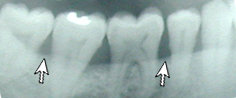

Healthy gums and bone.